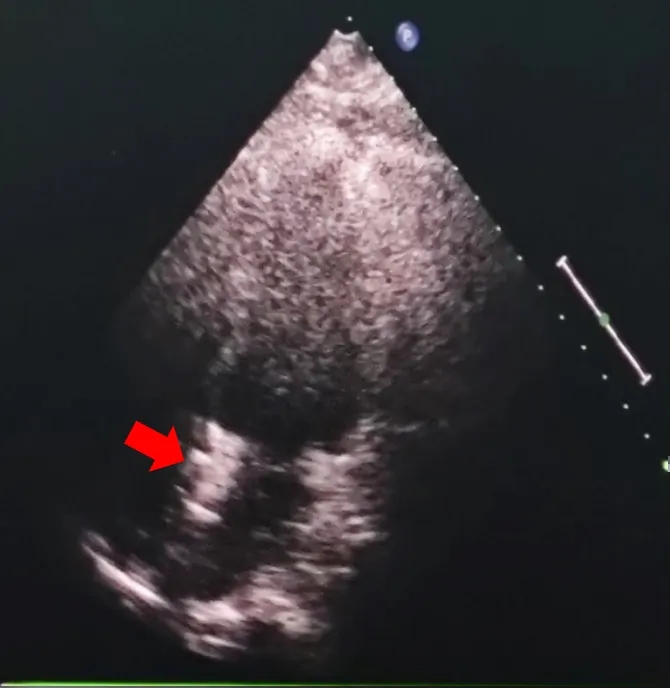

术后超声

超声下可见封堵器左右盘面牢牢贴靠房间隔,且无残余分流,封堵成功